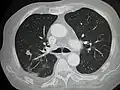

Initially, nearby lymph nodes are struck early.[10] The lungs, liver, brain, and bones are the most common metastasis locations from solid tumors.[10]

- Lung metastasis: cough, hemoptysis and dyspnea[10] (shortness of breath)

Metastatic tumors are very common in the late stages of cancer. The spread of metastasis may occur via the blood or the lymphatics or through both routes. The most common sites of metastases are the lungs, liver, brain, and the bones[10]